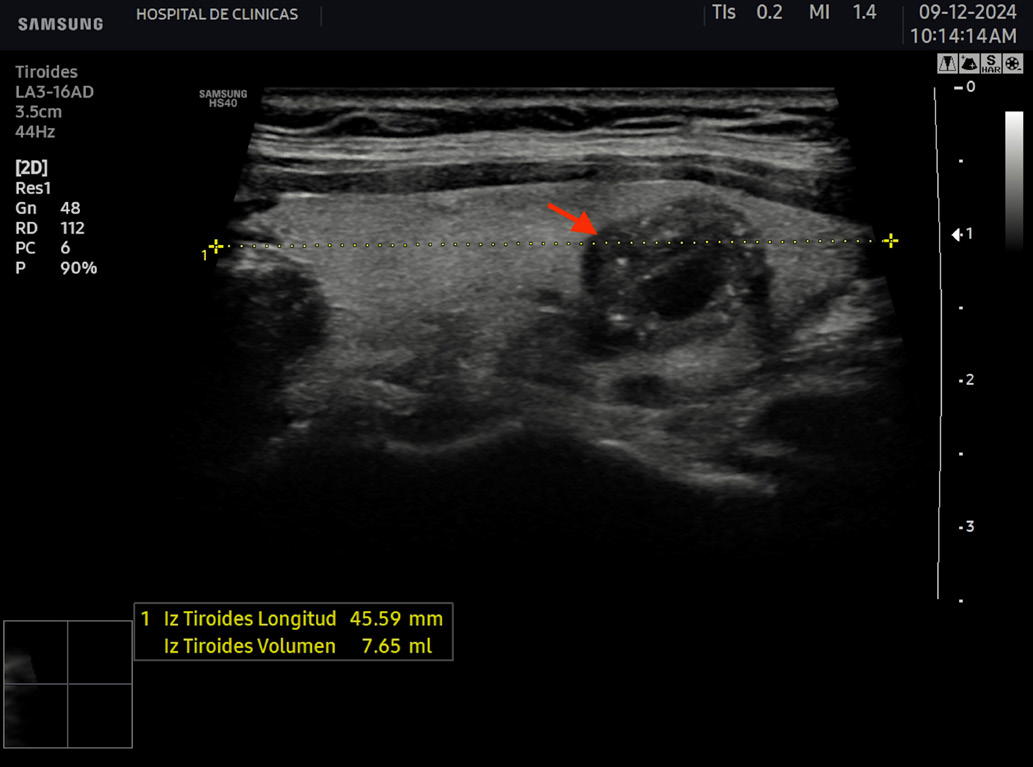

La eco estructura es homogénea, los márgenes son regulares y presenta una cápsula ecogénica, su vascularización es escasa. El rango de referencia para una tiroides normal es de entre cinco y diez vasos visibles dentro de la exploración de cada lóbulo valorado con Doppler color2. Se ha descripto que hasta un 50% de los individuos presentan lóbulo piramidal (Figura 3a y 3b). Este sector, en general, es similar en ecogenicidad, homogeneidad y vascularización al istmo y los lóbulos. En la superficie posterior de los lóbulos tiroideos, especialmente en el segmento inferior, puede visualizarse el tubérculo de Zuckerkandl, un ejemplo de este se puede observar en la figura 4a y 4b. Este es un tabique hiperecogénico fibroso que a menudo genera sombra posterior. Se forma por la extensión del tejido tiroideo de las áreas laterales de los lóbulos hacia el sector posterior, y a menudo exhibe una disminución de la ecogenicidad detrás del mismo. Este proceso puede imitar una lesión tiroidea o paratiroidea y causar dificultades en la interpretación2.